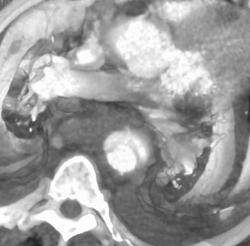

Diagnosis

Coronary Artery Scanning